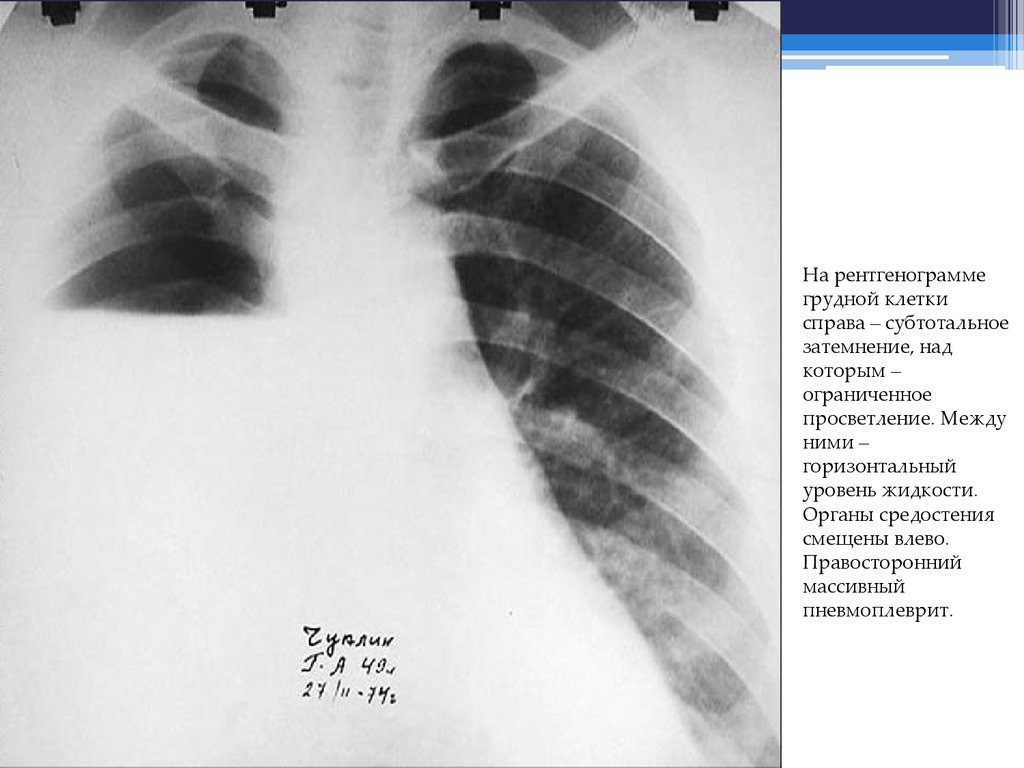

На рентгенограмме грудной клетки – субтотальное затемнение справа в

сочетании с ограниченным апикальным просветлением. Между ними горизонтальный уровень жидкости. Органы средостения смещены влево.

Правосторонний массивный пневмоплеврит.

На рентгенограмме

грудной клетки

справа – субтотальное

затемнение, над

которым –

ограниченное

просветление. Между

ними –

горизонтальный

уровень жидкости.

Органы средостения

смещены влево.

Правосторонний

массивный

пневмоплеврит.